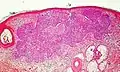

Differential diagnoses

| Differential diagnosis | Pathological Features | Image |

| Hair follicles | Peripheral sections may look like nests, but do not display atypia, nuclei are smaller, and serial sections will reveal the rest of the hair follicle. | ![]() |

| Squamous-cell carcinoma of the skin | Squamous-cell carcinoma of the skin is generally distinguishable by for example relatively more cytoplasm, horn cyst formation and absence of palisading and cleft formations. Yet, a high prevalence means a relatively high incidence of borderline cases, such as basal-cell carcinoma with squamous cell metaplasia (H&E stain at left in image). BerEP4 staining helps in such cases, staining only basal-cell carcinoma cells (right in image). | ![]() |

| Trichoblastoma | Absence of cleft, rudimentary hair germs, papillary mesenchymal bodies. | ![]() |

| Adenoid cystic carcinoma | Lack of basaloid cells disposed in peripheral palisades; adenoid-cystic lesion without connection to the epidermis; absence of artefactual clefts | ![]() |

| Trichoepithelioma[notes 1] | Rims of collagen bundles, calcification, follicular/sebaceous/infundibular differentiation and cut artefacts. Cytokeratin (CK)20+, p75+, Pleckstrin homology-like domain family A member 1 + (PHLDA1+), common acute lymphoblastic leukemiaantigen + (CD10+) in tumor stroma, CK 6-, Ki-67- and Androgen Rceptor- (AR-) | ![]() |

| Merkel cell carcinoma | Cells arranged in a diffuse, trabecular and/or nested pattern, involving also the subcutis. Mouse Anti-Cytokeratin (CAM) 5.2+, CK20+, S100-, human leukocyte common antigen- ( LCA-), thyroid transcription factor 1- (TTF1-) | ![]() |